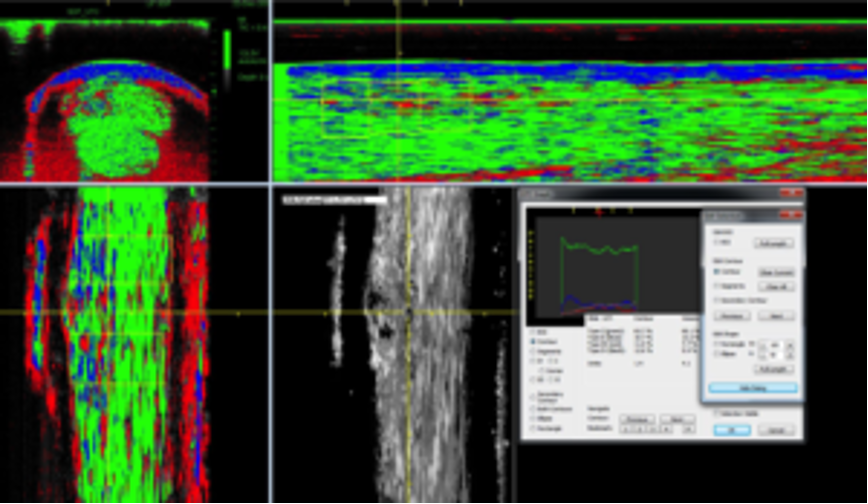

Waarom Franklin Lashley zo graag met het UTC-apparaat werkt, legt hij uit: “Tijdens het traject wat  de probe langs het been aflegt, wordt om de 0,2mm een beeld gemaakt dat direct wordt verwerkt door de software in de computer. Hiermee kan er met één scan zowel een dwars- als lengtedoorsnede worden gemaakt. Vervolgens kan je op de computer zelfs een beeld van de pees in elke gewenste richting bekijken. Dit geeft een 3D-beeld van de peesinrichtingen die je anders alleen bij het doorsnijden tijdens een operatie zou kunnen zien. Een groot voordeel van de UTC is dat deze ook een berekening kan maken van de kwalitatieve toestand van de pees. Hiermee kunnen de belastbaarheid en kwaliteit van het aanwezige weefsel worden bepaald. Dit geeft aan in hoeverre de pees weer gebruikt kan worden na bijvoorbeeld een blessure, zware belasting of rust. Ook kunnen we op deze manier al kleinere (subtiele) veranderingen opsporen nog voordat deze overgaan in een echte verscheuring.”

UTC met kleurcodering

1. groen voor normaal gerangschikte peesbundels

2. blauw voor meer golvende peesbundels

3. rood voor fibrillaire (kleinere/onvolwaardige) bundels

4. zwart voor met name vocht